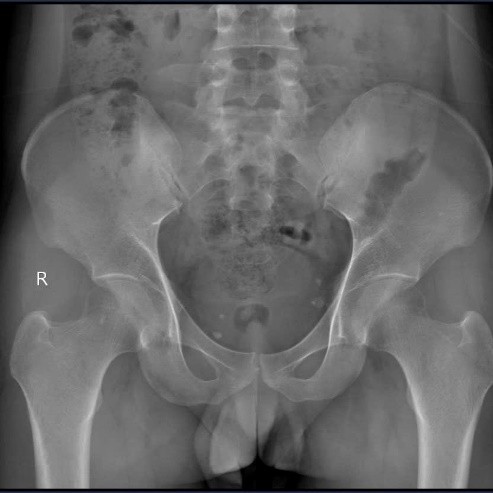

Ngày 17/11/2025, người bệnh tái nhập viện trong tình trạng ổn định. Siêu âm cho thấy song thai 34 tuần, tim thai tốt, nước ối bình thường. Người bệnh mong muốn được nối lại bàn tay để phục hồi chức năng sinh hoạt và chăm sóc con sau sinh.